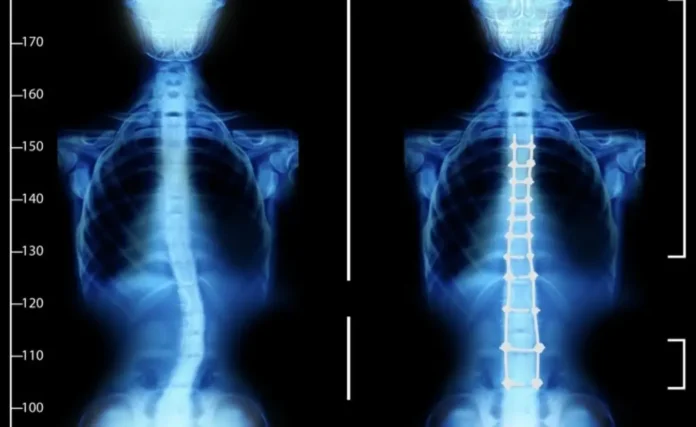

Entre las principales malformaciones detectadas en Veracruz están:

• Labio y paladar hendido

• Microcefalia

• Mielomeningocele (una forma de espina bífida)

Especialistas advierten que las malformaciones pueden tener múltiples causas, desde factores genéticos hasta condiciones ambientales, exposición a sustancias tóxicas o infecciones durante el embarazo.